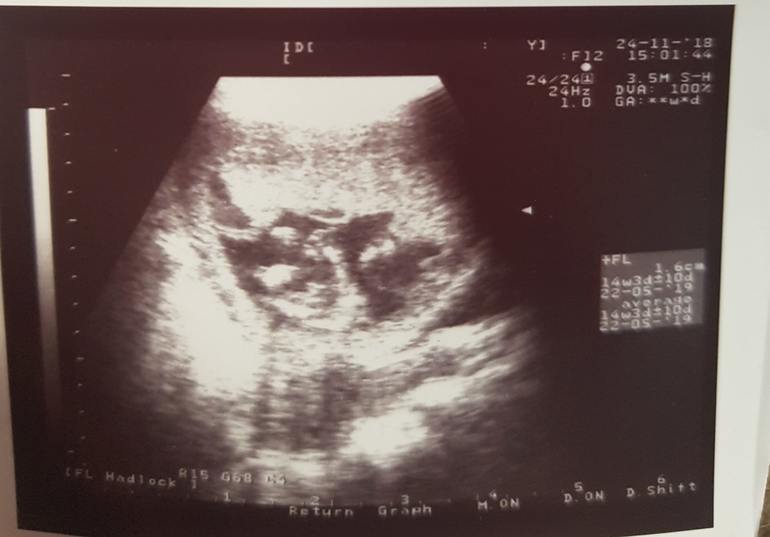

15 недель,пол малыша,,опять я,,,))Что скажете ???🙄🙄🙄

Неужели вам не могут сделать нормальный снимок узи? 😑 Я всегда просила сделать мне снимок в качестве подтверждения когда узист озвучивал пол. И никогда не было таких размазанных снимков, где фиг поймёшь что и как. В след раз просите уже нормальное фото чтоб людям не ломать глаза 😅 Вот мой в 15+3.

Если бы было фото другое и потверждение определенного пола ,я бы точно всех бы тут не мучала,а точно уже перекрасила кружочек или розовый или синий😅

Ну вот такой сделали узи старенькое,,,пол непонятно какой,,,типа сама догадайся😂😂вот с вашей помощьб пытаюсь истиу найти🤗🤗🤗

Да я просто к подруге пошла,из за ттг высокого чтоб сердечко послушать,а она мне наискала между ножек что то,,но сама не уверенна,,,а я мучаюсь теперь🤨🤨🤨

Но вот по вашему снимку узи, если то на что я смотрю это промежность, то на мальчика больше ставка чем на девочку 😊😅

Это фото из под попы?

Ага это жопка ножки а между ними треугольничек торчит

Треугольник очень далеко от жопки... это не писюн

Окозался писюн ,,,вам на радость!!!

По этой фотке четко мальчик!

Вижу мальчика очень отчетливо.

Если это фотка с низу то писюн видно, да!😊

А мне кажется это не писюн, а носик, просто там же ляли пополам сложен, а писюн левее на фото и это девочка😂 голова между ножек, у меня на подобии УЗИ есть, там писюн совсем по другому, но фотку не нашла пока, найду покажу

Это попка и ножки головы ьам вообще невидно😋🤣🤣🤣

если попа и ножки то торчит писюн..... я это три раза видела.... хотя последний не такой как первые два